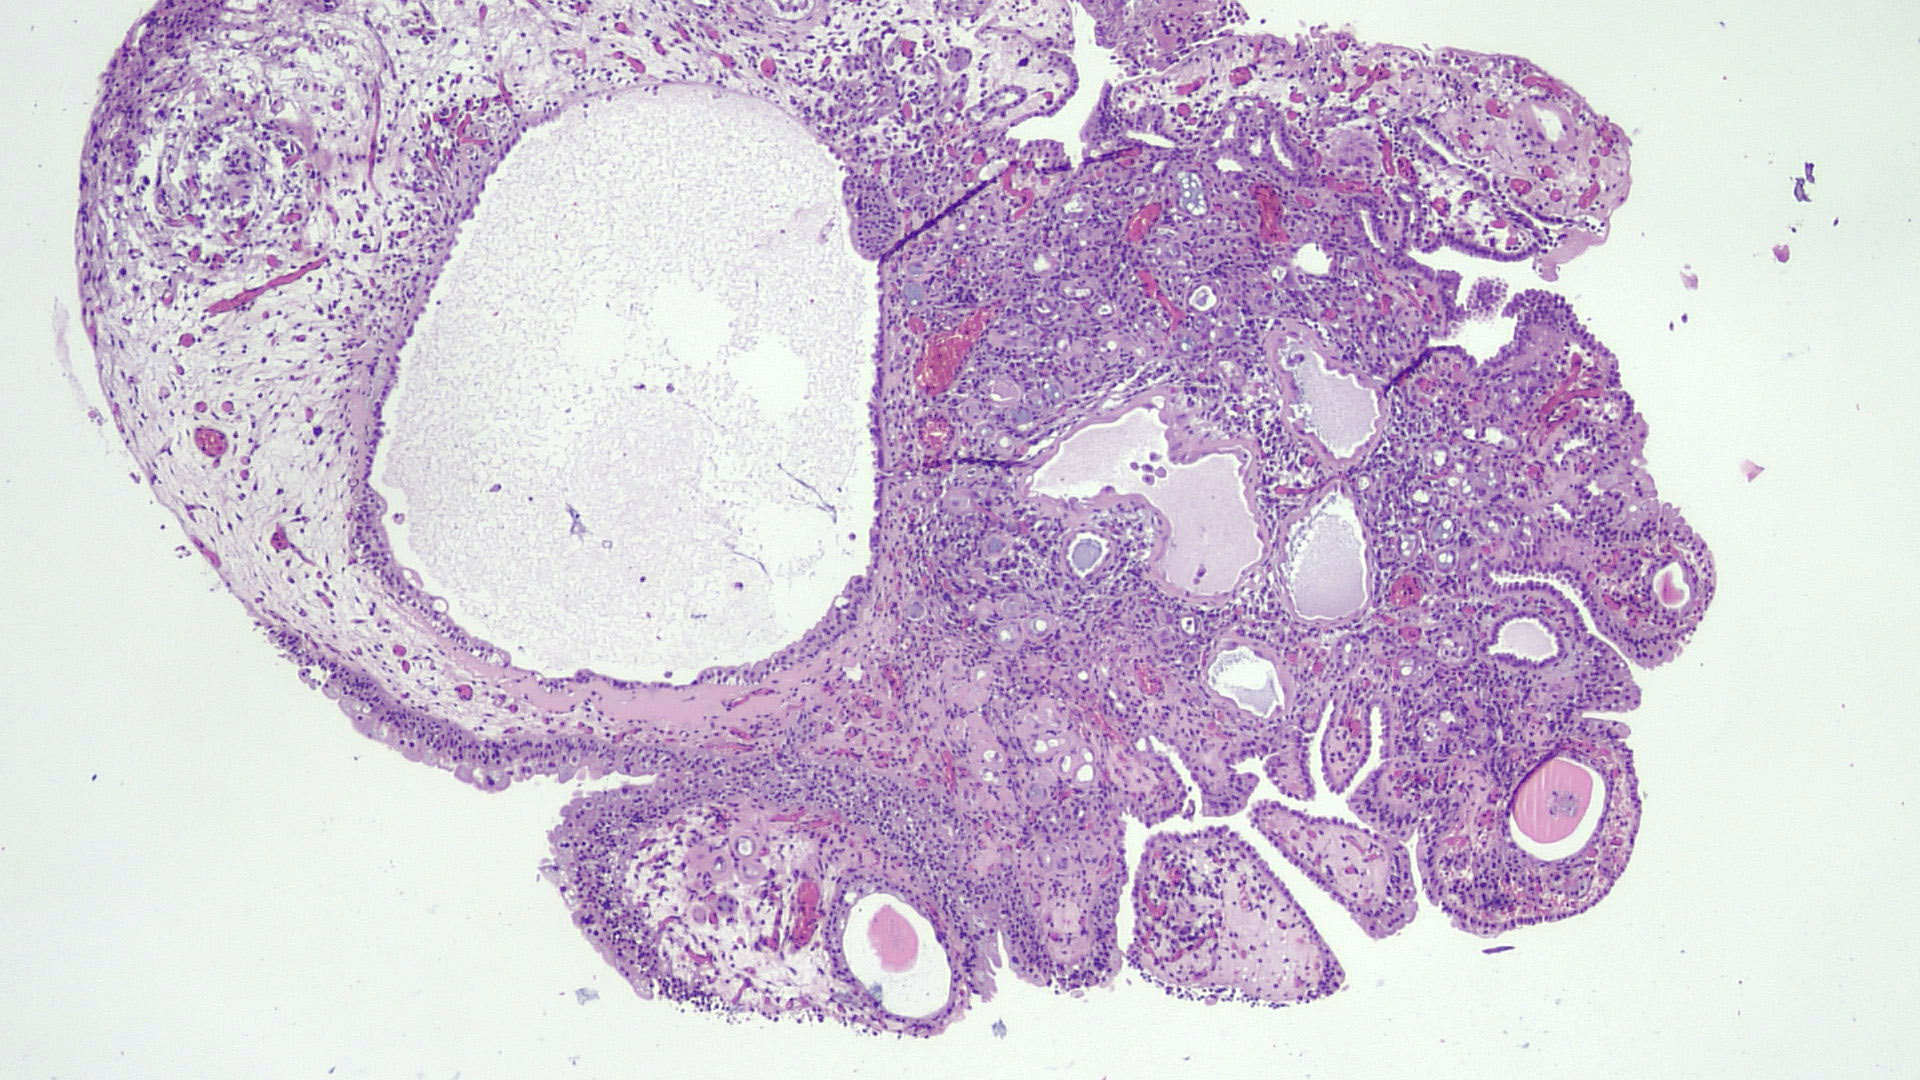

- Tubules lined by simple cuboidal, flattened or hobnail cells, forming an exophytic papillary or endophytic lesion (Urology 2016;95:29)

- Associated acute and chronic inflammation and edema in the stroma; lack of desmoplastic reaction

- Many morphologic variants (multiple patterns may occur in the same cases): papillary, tubular, tubulocystic, polypoid, flat, fibromyxoid, signet ring cell-like (Mod Pathol 2013;26:792)

- Hyaline rim surrounds the tubules (PAS positive thickened basement membrane) (Adv Anat Pathol 2019;26:171)

- No mitotic activity

- Scant cytoplasm, finely granular uniform chromatin; usually inconspicuous nucleoli (Ann Diagn Pathol 2019;38:11)

- Only occasionally solid areas, rare clear cells, blue mucin within the tubules present

- Sometimes atrophic tubules filled with eosinophilic colloid-like material mimicking thyroid follicles and mesonephric hyperplasia

Microscopic (histologic) images